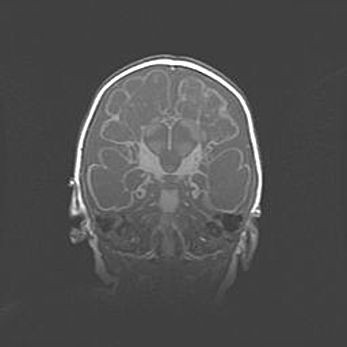

Аномалия Денди-Уокера. Признаки гипоплазии мозолистого тела.

Возраст: 5 месяцев 3 дня

Вес: 5550 г

Пол: мужской

Окружность головы: 39 см

Срок гестации: 40 недель

Аномалия Денди-Уокера – это порок развития головного мозга, для которого характерна триада симптомов: гипотрофия или аплазия червя мозжечка и/или полушарий мозжечка, расширение четвёртого желудочка с формированием ликворной кисты задней черепной ямки, гипертензионная гидроцефалия различной степени.

Гипоплазия мозолистого тела относится к дефектам внутриутробного этапа развития мозговой ткани, возникающим в процессе закладки структур головного мозга, что происходит на начальных этапах развития эмбриона.